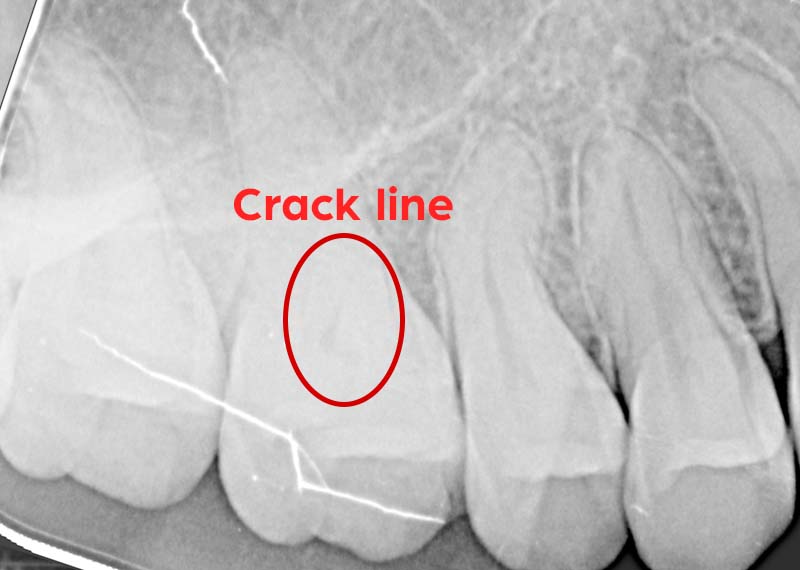

Trigger: When biting down or releasing a bite

Cause: Cracked tooth